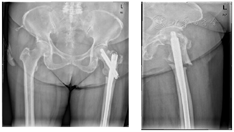

入院后完善检查,明确无手术禁忌证后,给予全身麻醉下行"左股骨粗隆下骨折骨不连髂骨取骨植骨内固定术"。手术方法:患者取仰卧位,左侧臀部垫高,常规消毒铺巾。沿原切口切开并适当延长,依次切开皮肤、皮下组织及深筋膜,钝性分离股外侧肌,显露并探查骨折断端,可见骨赘增生,骨折间隙纤维软组织充填。清除骨折间隙瘢痕组织,髂骨取骨修剪成颗粒骨充填,应用7孔锁定接骨板加强固定。手术时间2小时,出血约200 ml。术后安返病房。交待患者停用双膦酸盐,改用特立帕肽,20μg/支,每日一次,每次一支,皮下注射。患者在术后1年实现骨折临床愈合。

患者常规在术后1、3、6及12个月共随访四次,在术后第12个月骨折临床愈合,左髋行走后不再疼痛,实现完全负重行走。